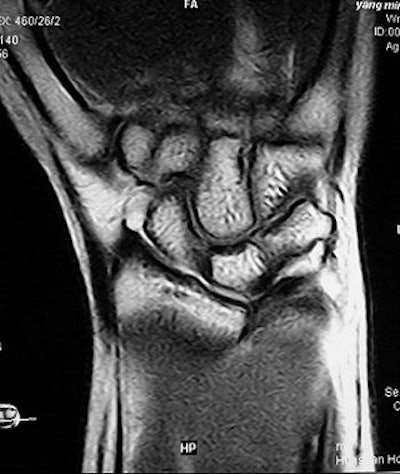

![]() |

| The advantages of direct MR arthrography included clear visualization of synovial reaction and chondromalacia, and marrow edema, said Shuang and Xiaoyuan in their RSNA presentation. Images courtesy of Dr. Chen Shuang. |

On MR arthrography, the readers saw high signal intensity of contrast media at the ulnar insertion or radius attachment of the TFCC. Synovial reaction, chondormalacia and marrow edema were also clearly depicted on T2-weighted imaging and direct MR arthrography.

Shuang and co-author Dr. Fen Xiaoyuan suggested that when assessing for peripheral TFCC tears, imagers would find more diagnostic value from the high signal intensity at the radius attachment than at the ulnar insertion. They concluded that direct MR arthrography can reveal the peripheral attachment of the TFCC. Shuang told AuntMinnie.com that direct MR arthrography is now the preferred modality for TFCC imaging at his institution.